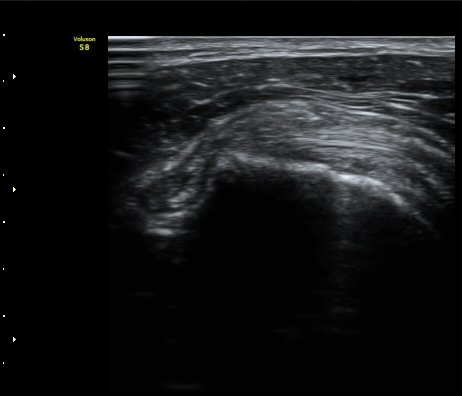

À̵ιڱ٠Ⱦ´Ü¸é°Ë»ç¿¡¼­ Á¡¾×³¶³» °í¿¡ÄÚ ¼®È¸È­ À½¿µµéÀÌ °üÂûµÊ(±×¸² 1, 2, 5)

¿ÜȸÀüÀÇ Á¦ÇÑÀ¸·Î °ß°©ÇϱٰÇÀÌ ¼öÆòÀ¸·Î °üÂûµÇÁö ¸øÇϰí À̵ιڱ٠ǥÃþ¿¡

¼®È¸È­ À½¿µÀÌ °üÂûµÊ(±×¸² 3)